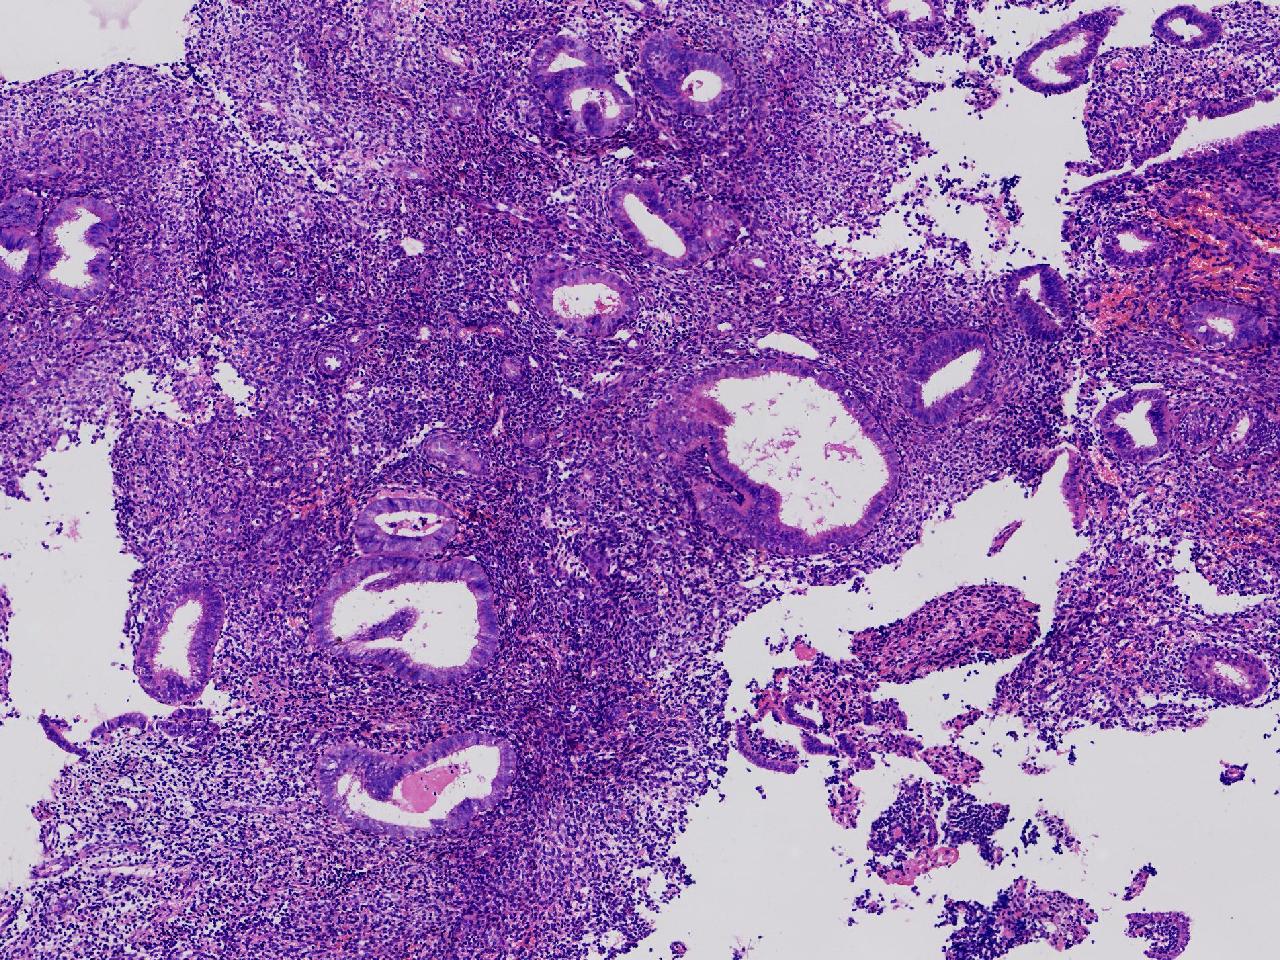

请教诊断。局灶够不够非典?

性别

女

年龄

44岁

阴道不规则出血20余日,彩超示:内膜线居中,厚15毫米。

子宫内膜

灰粉色不整形软组织多块,3X2X1厘米。

不够非典

有输卵管上皮化生,感觉不够非典。